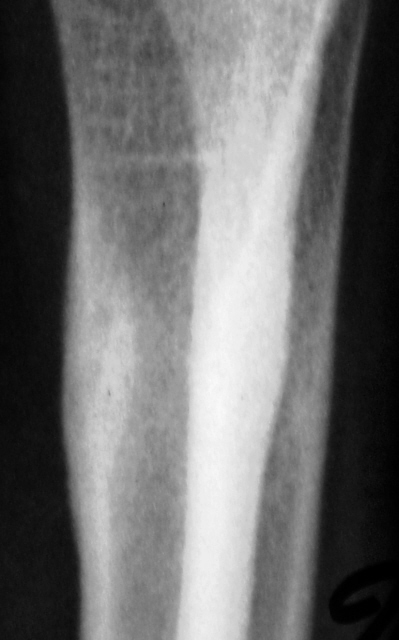

А с этим (помечено стрелками), что будем делать?

ИзображениеИзображение

Коллеги! меня тоже смущает участок, выделенный Валентином Львовичем стрелочками. Имеются округлой формы, мелкие участки перестройки костной ткани литического типа. Кортикальный слой муфтообразно утолщен с периоссальной реакцией. А нет ли там объемного образования?

Меня тоже смущает, и очень. Отправляйте к детским онкологам, пусть они контролируют. Основание: диафиз лучевой кости бульбообразно расширен ("поддут"), структура кости уплотнена муфтообразно/"пояском", менее выраженные, чем по переднему стенке кости, но аналогичные изменения отмечаются и по задней стенке диафиза, плюс периостальная реакция в прямой проекции.